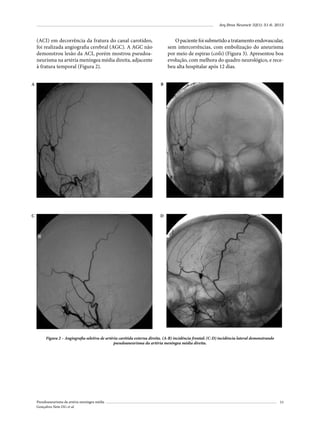

Telefone: (55 11) 2176-7000

E-mail: guilhermebraguiar@yahoo.com.br

Pseudoaneurisma da artéria meníngea média

Gonçalves Neto DG et al.

Arq Bras Neurocir 32(1): 57, 2013

Erratas